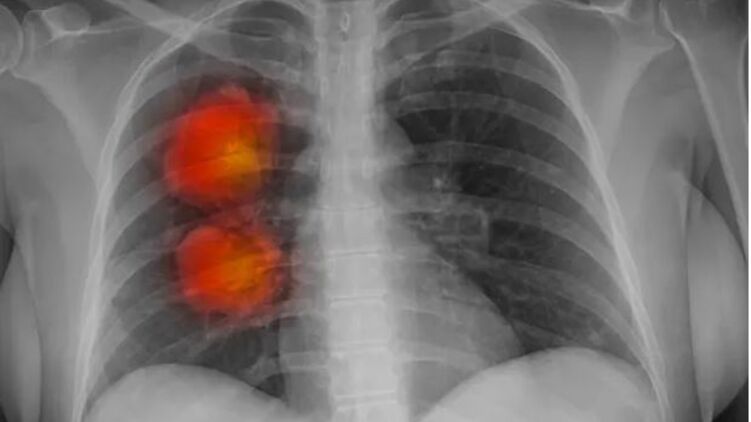

На долю рака легких приходится 21% смертей от рака в Великобритании. Фото: Cultura Creative/Alamy

Инструмент искусственного интеллекта был разработан экспертами фонда Royal Marsden NHS, Института исследования рака в Лондоне и Имперского колледжа Лондона. Он может определить, являются ли аномальные новообразования, обнаруженные на КТ, злокачественными.

Команда использовала компьютерную томографию около 500 пациентов с большими узлами в легких для разработки алгоритма искусственного интеллекта. Этот метод может извлекать жизненно важную информацию из медицинских изображений, которые трудно заметить человеческому глазу.

Согласно первоначальным результатам, модель ИИ, по-видимому, точно идентифицирует раковые крупные узелки в легких.